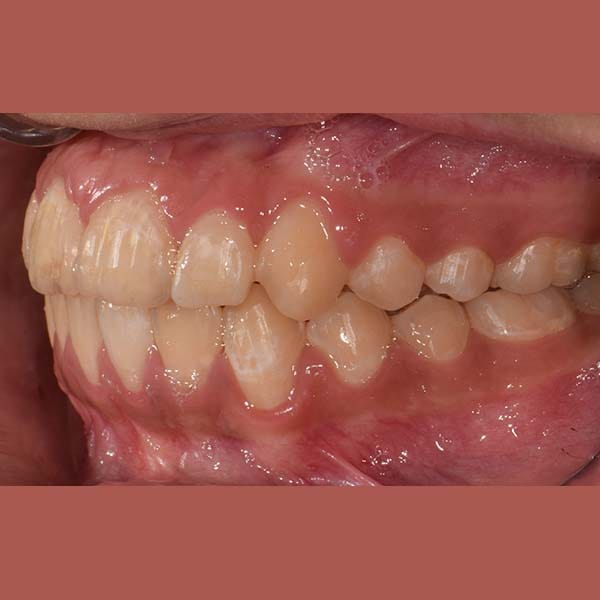

بعد شرح أن قلع الأسنان يكون ضرورياً أحياناً، وبعد الفحص الدقيق، طمأن الدكتور خالد الكاتب الأم بأنه لحسن الحظ، حالة ابنتها تسمح بالعلاج دون قلع. اعتمدت الخطة على توسيع الفكين لفتح مسافة كافية لرصف الأسنان. تم اختيار تقويم الدايمون (ذاتي الربط) لهذه المهمة، حيث يعتبر مثالياً لهذا النوع من المعالجات التي تتطلب توسيعاً فعالاً.

كما تظهر الصور، نجحت الخطة العلاجية في رصف الأسنان بشكل ممتاز وتحقيق ابتسامة جميلة ومتناسقة. وكالعادة، أصبح بإمكان صديقتنا الشابة أن تبتسم لوالدتها ولكل من حولها بثقة وسعادة.